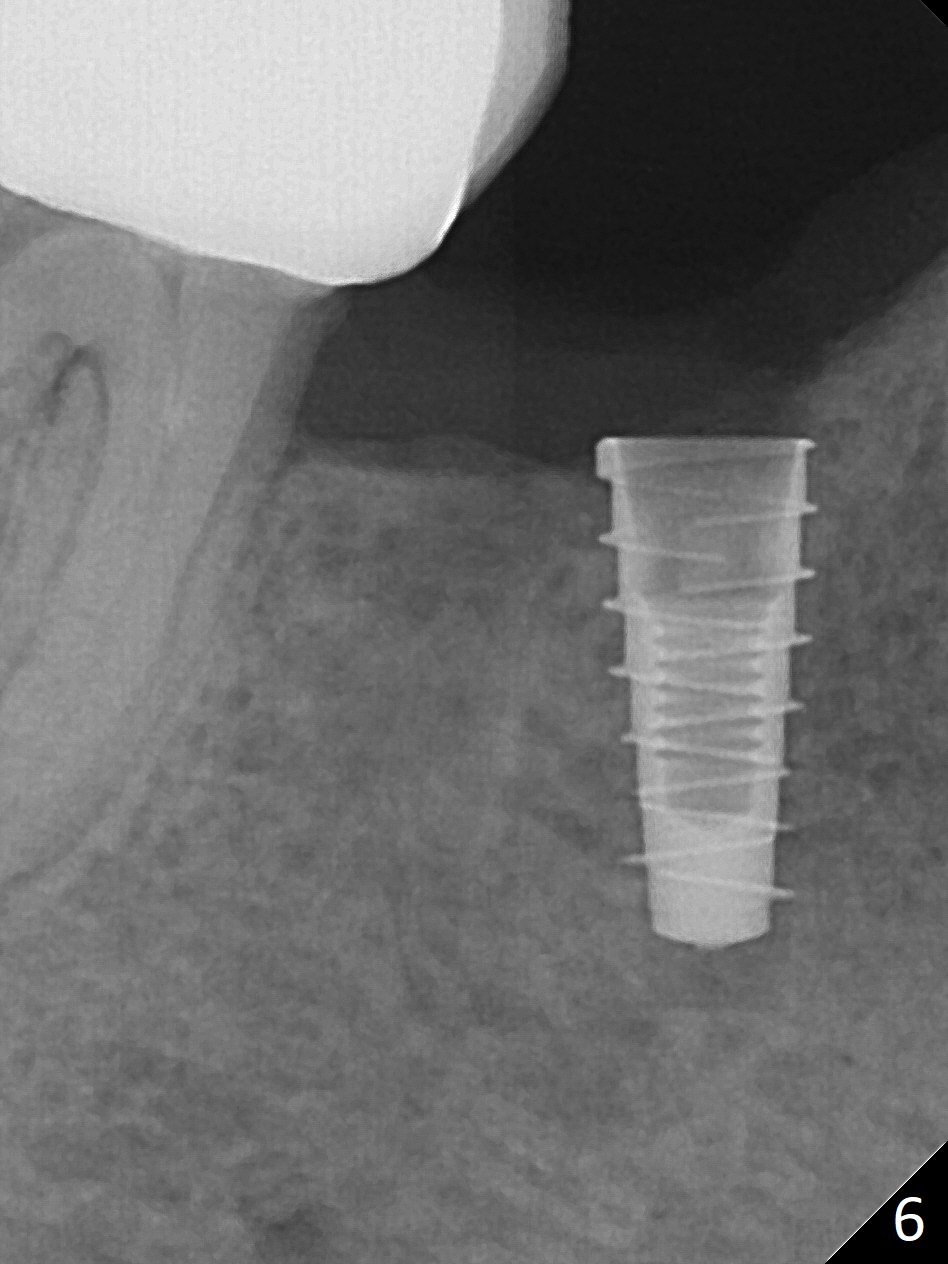

The patient returns for implant placement 11 months post extraction of #28 and 29. With flapless manner, initial osteotomy happens to drop into the original socket of #28 (Fig.4). After use of 3.3 mm Magic Drill (MD) and Final Drill for 15 mm, a 4x11 mm dummy implant is placed (Fig.5). It appears that the implant is long for the site (red dashed line: Mental Loop). However, a definitive implant (4x9 mm, IBS) has difficulty to reach its depth (Fig.6). After several rounds of untorque and retorque, the implant does not seat completely (Fig.7, implant driver disengagement) with autogenous bone placed distal (>). Retrospectively, a larger MD should have been used (3.8 mm) for complete seating in the dense bone. In fact she is post breast cancer treatment with 50% chance of relapse. The patient returns for follow up 1.5 months postop (Fig.8). The wound has healed. Impression is taken 5 months postop (Fig.9). When the crown is cemented, food impaction is an issue between the implant crown and crown at #30. Since the tooth #30 is mesially tilted with distal open margin and apical infection, the tooth will be extracted. Osteotomy is going to be initiated in the mesial slope of the mesial socket (Fig.9 red line). An implant will be placed more or less in the mesial socket (green box).